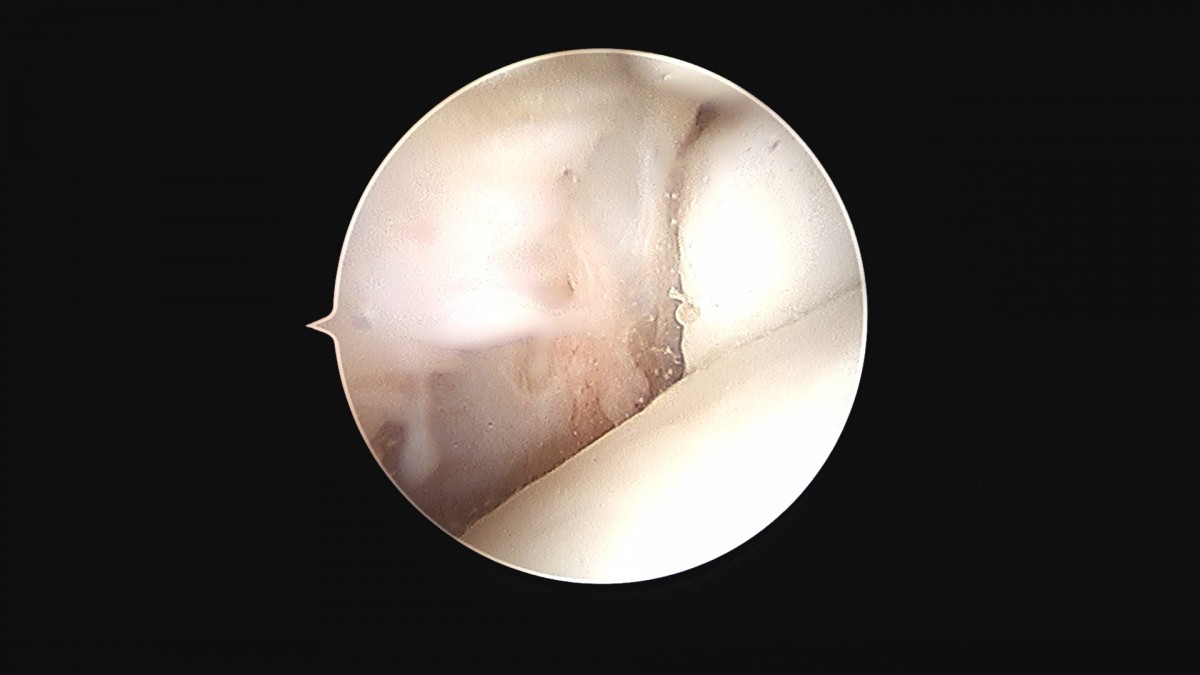

이재상원장님 발목 활액막 절제술 및 인대 봉합술 신진O 환자

dae765e4d9ac96aee867c9d6292d8784_1758003733_6364.jpg